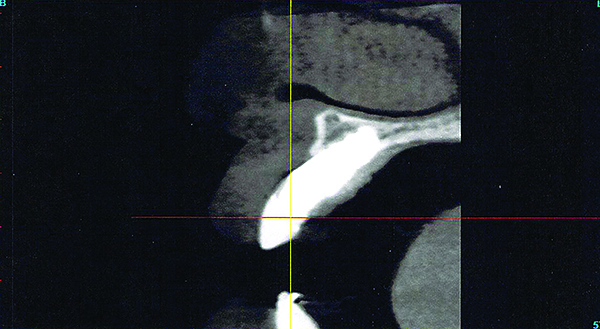

A implant restoration with a buccal dehiscence of bone and soft tissue caused by poor implant positioning, lack of keratinized tissue prior to implant placement, and soft tissue recession post implant restoration.

Figure 8

The same implant in Fig 8, 7 years following treatment, which included two autogenous connective tissue grafts and a bone augmentation surgery with a combined allograft and xenograft mixed with two biologics.

Figure 9